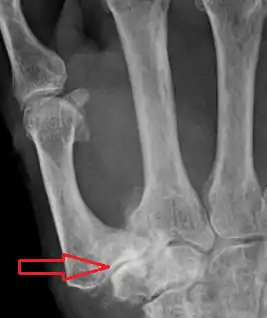

Stage 3:

- > 1/3 subluxation of the joint

- Osteophytes, > 2 mm in diameter, are present (usually adjacent to the volar and dorsal facets of the trapezium)

- Slight joint space narrowing